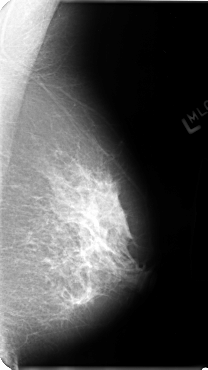

B_3128_1.LEFT_MLO

LEFT_MLO LINES 4800 PIXELS_PER_LINE 2696 BITS_PER_PIXEL 12 RESOLUTION 50 NON_OVERLAY